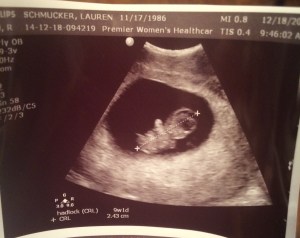

I had Lauren send me the ultrasound picture of the baby, soon to be known as “Fig”, and is now known as Evan. I instantly fell in love. A love that grows daily, for him, and for his mother.